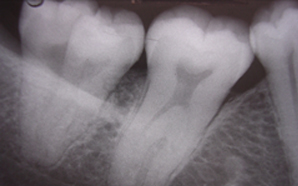

SERVICIOS